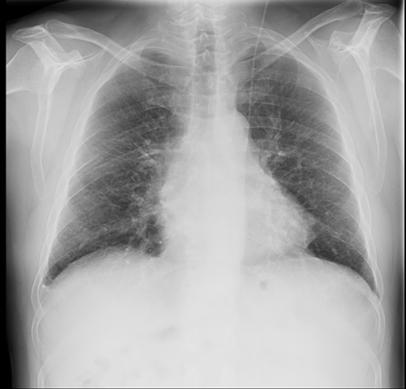

En cuanto a las pruebas de imagen, la afectación será típicamente en campos medios y superiores y en regiones perihiliares y peribroncovasculares, con opacidades quísticas, bronquiectasias por tracción y reticulación. Las estructuras quísticas encontradas en las formas fibróticas de la sarcoidosis suelen ser de mayor diámetro que las lesiones tradicionales de panal³. Podremos encontrar estos hallazgos asociados a adenopatías hiliares y/o mediastínicas, en ocasiones calcificadas en “cáscara de huevo” así como a opacidades nodulares o retículonodulares bien definidas e incluso consolidaciones con una distribución paraseptal o peribroncovascular típica. El PET-TC puede emplearse como una herramienta para detectar enfermedad activa en pacientes seleccionados⁴ .